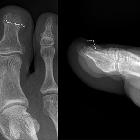

Nagelklammer

am Großzehennagel im Röntgenbild zur Anhebung der Nagelränder bei einwachsendem Nagel.